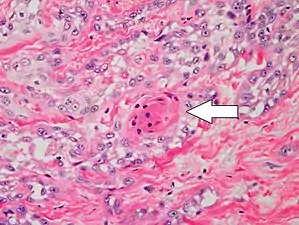

Histopathologically, the epidermis in cSCC in situ (Bowen's disease) will show hyperkeratosis and parakeratosis. There will also be marked acanthosis with elongation and thickening of the rete ridges. These changes will overly keratinocytic cells which are often highly atypical and may in fact have a more unusual appearance than invasive cSCC. The atypia spans the full thickness of the epidermis, with the keratinocytes demonstrating intense mitotic activity, pleomorphism, and greatly enlarged nuclei. They will also show a loss of maturity and polarity, giving the epidermis a disordered or "windblown" appearance.

Two types of multinucleated cells may be seen: the first will present as a multinucleated giant cell, and the second will appear as a dyskeratotic cell engulfed in the cytoplasm of a keratinocyte. Occasionally, cells of the upper epidermis will undergo vacuolization, demonstrating an abundant and strongly eosinophilic cytoplasm. There may be a mild to moderate lymphohistiocytic infiltrate detected in the upper dermis.[12]

Histopathology of squamous-cell carcinoma in situ (black arrow), compared to normal skin, showing marked atypia.

Squamous-cell carcinoma in situ, showing prominent dyskeratosis and aberrant mitoses at all levels of the epidermis, along with marked parakeratosis.[12]